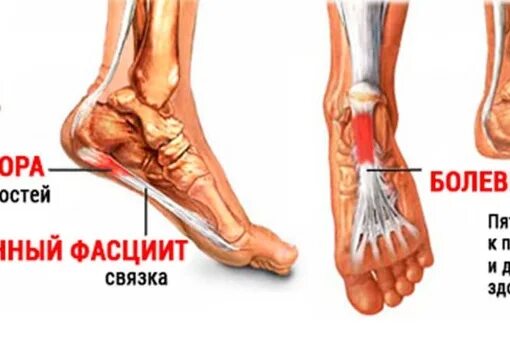

Пяточная шпора проходит сама по себе